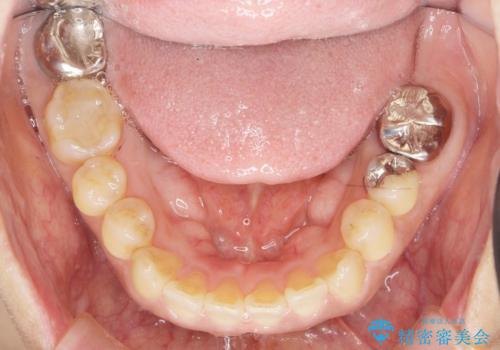

歯周病に対する全体治療

- 近医で「重度の歯周病です、入れ歯にする必要がある。」、と言われ入れ歯以外の方法がないか相談にみえられました。

再生治療、歯周外科を行うことで歯周病治療を行い、残すことのできる歯の歯周環境を整える。

残すことのできない歯は抜去したのち骨造成を含めたインプラント治療を行い、しっかりとした咬合関係を確立していきます。

治療期間はかかりましたが、しっかりと歯周病治療・インプラント治療を行ったおかげで歯周病の状態は非常に良くなり、安定した咬合関係を確立することができました。